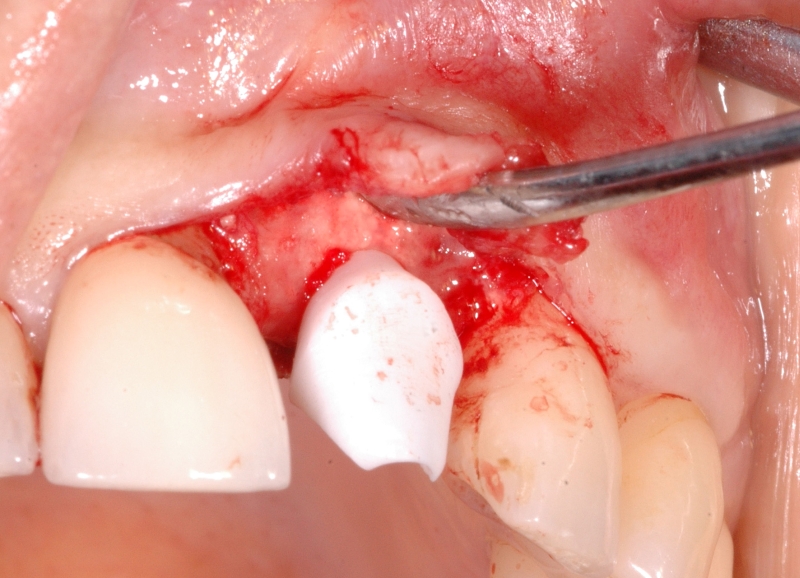

13/18 - Further soft tissue augmentation with mucoderm®GBR together with soft tissue augmentation with mucoderm® and maxresorb® - Dr. S. Scherg

14/18 - Wound closure and mounting of provisional prosthesisGBR together with soft tissue augmentation with mucoderm® and maxresorb® - Dr. S. Scherg